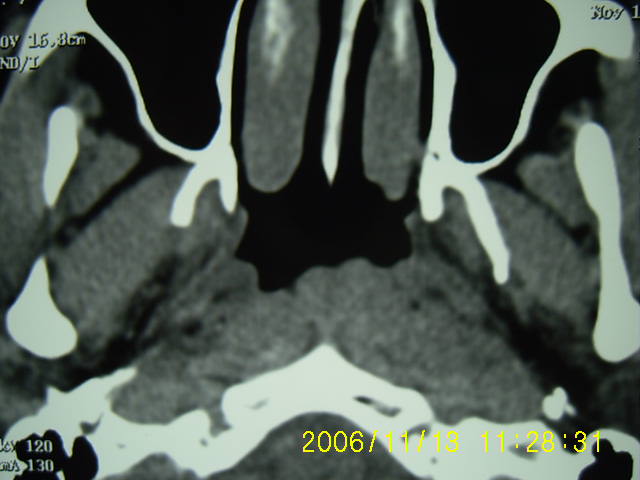

以下是引用zyx168在2006-11-13 13:15:00的发言:[br]左侧咽隐窝变浅,咽后壁软组织(头长肌)肿胀,左侧咽旁间隙推移变小.[br]结合临床,双侧颈部淋巴结肿大,考虑为左侧鼻烟癌.

以下是引用刘明在2006-11-13 12:47:00的发言:[br]左侧咽后壁软组织肿块,咽隐窝消失,首先考虑鼻咽癌